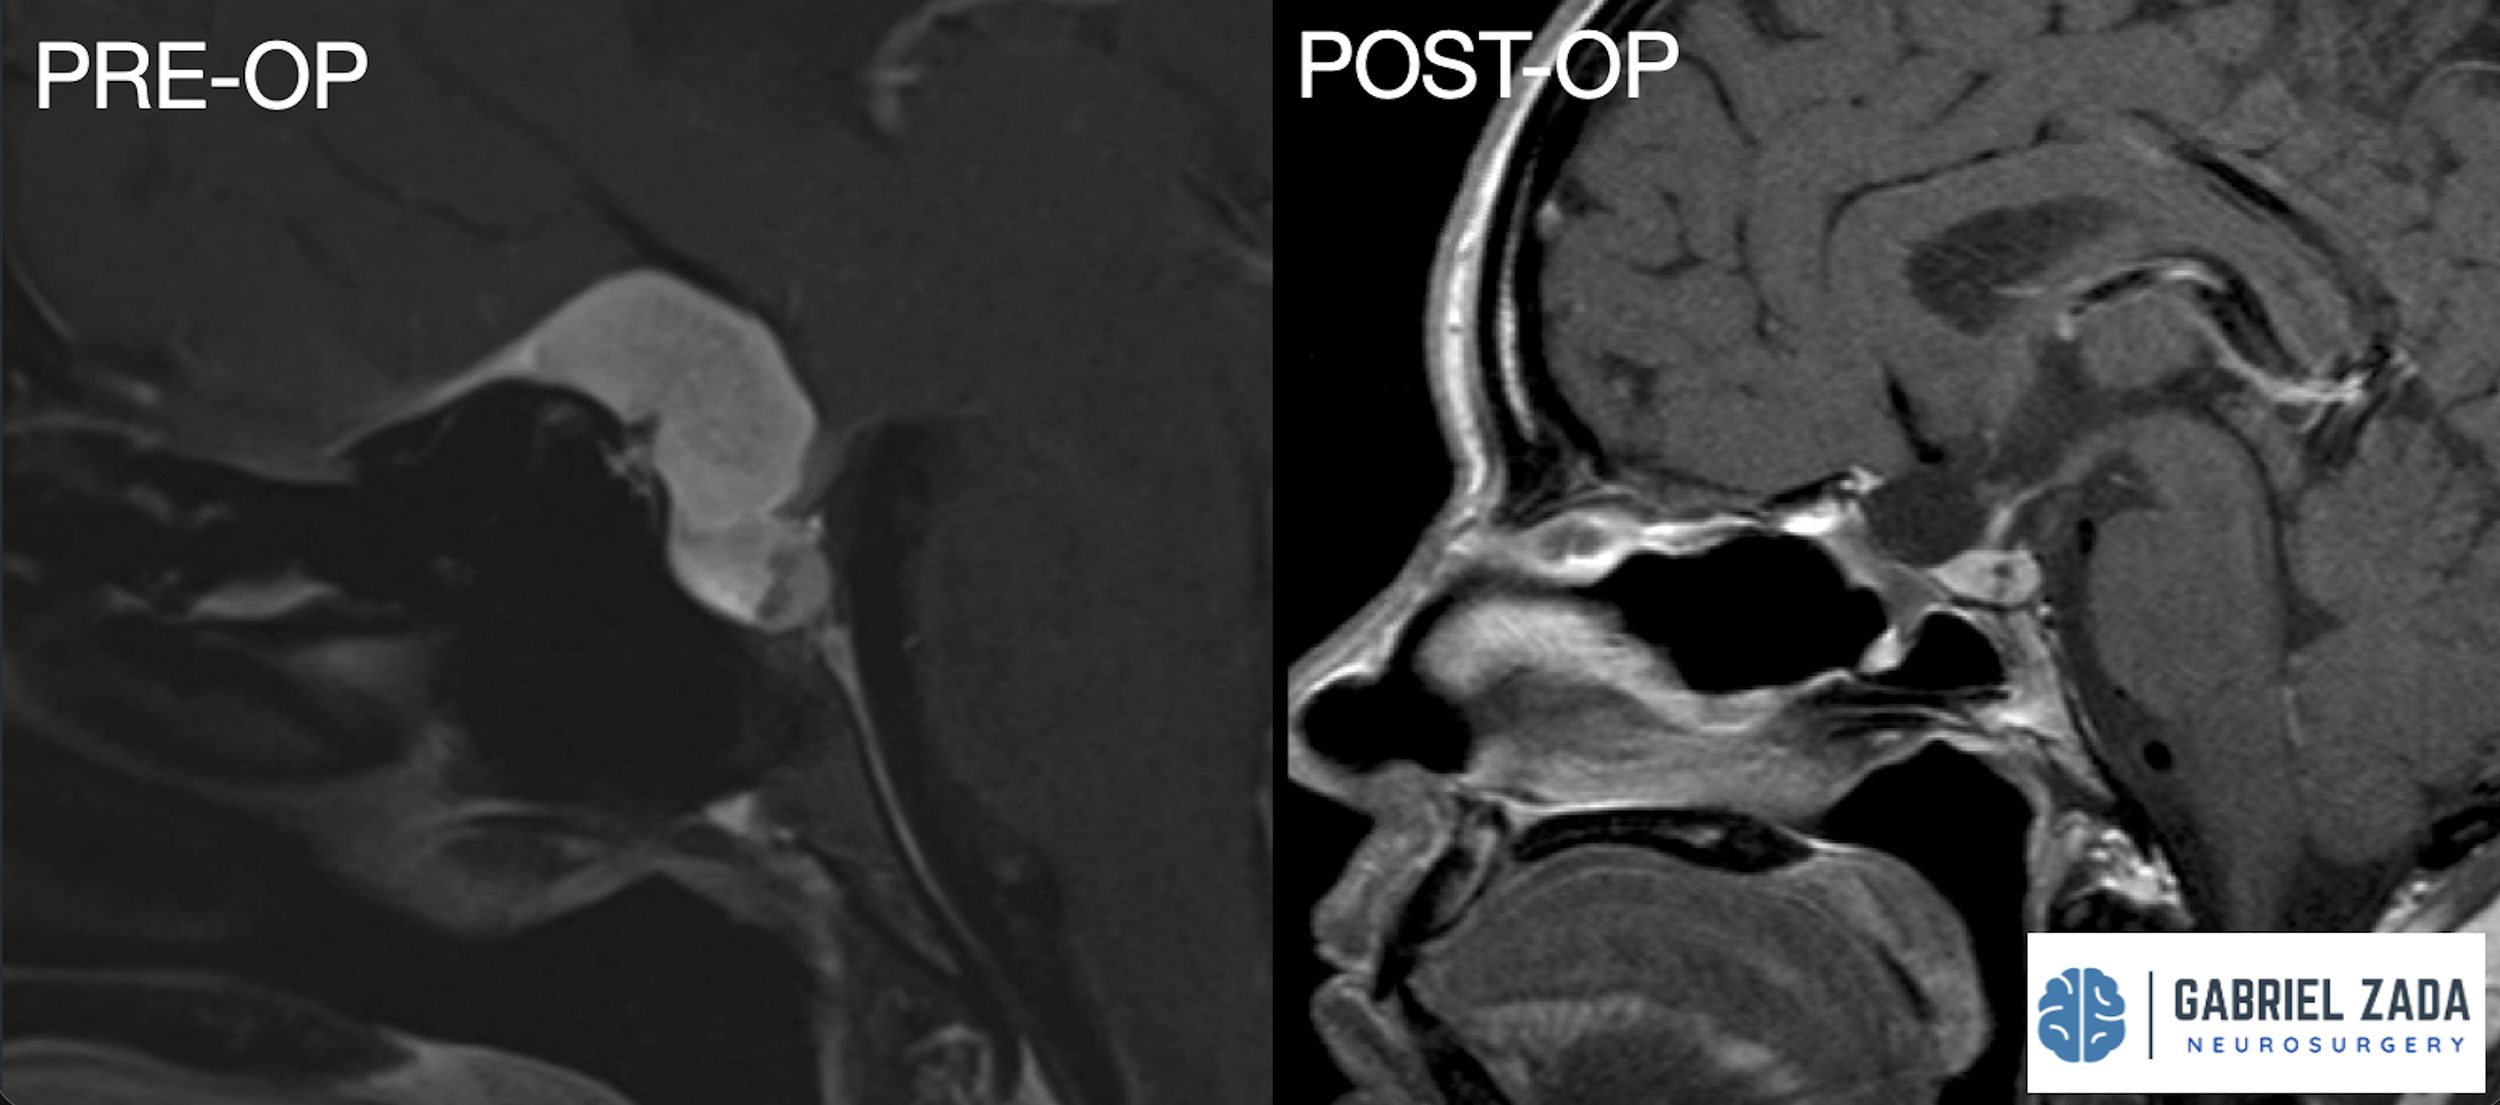

Explore this comprehensive gallery featuring pre‑ and post‑operative imaging of patients with skull‑base tumors treated by Gabriel Zada, MD, MS, FAANS, FACS. These cases highlight Dr. Zada’s expertise in advanced neurosurgical techniques and outcomes.

*Representative cases shown for educational purposes. All images de-identified. Individual results vary.